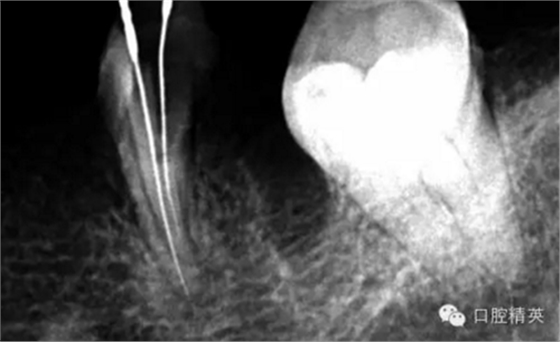

近中兩根試尖,預備根管15分鐘。

這個也是我目前接到最有難度的器械分離病例,從片子上看近中器械分離兩節(jié),曾在外院做過干尸,有七年。當看到這個病例時我沒有多大的把握,因為我是身處基層,無顯微,無放大。我只有抱著試一試的態(tài)度,但是她是我們院內(nèi)員工,壓力很大。

現(xiàn)在開始看第二張片子我疏通的遠舌根,有點問題哦!~

根尖孔偏移,或者是片子角度問題,導致我們很難判斷,感覺像是測穿。但是我們有根測儀(前提它是好的),因為根測儀是我們目前對根管測量最具有說服力,也是最為客觀事實的。根測儀沒有顯示一探入根尖下三分之一顯示“over”的情況(我用的是登士博根測儀)根管內(nèi)無滲出,可以測出根管的長度。那就證明工作長度的存在,和可信。在看看正題的近中根的器械,我想問問大家覺得是什么器械??

近中舌根疏通,兩根分離的器械都在近中舌根。花費2個多小時。將它疏通下去還是離不開較長的時間,也就是耐心,它真的很重要哦!~第二個我覺得器械分離的疏通,就是在于能否建立旁路,那么怎么去建立這條路。我個人覺得首先挫的選擇,是k挫,是c+,還是別的什么。我的首選是8號c+,因為它夠硬,8號的k挫太軟,沒有辦法擴下去,很容易碰到根內(nèi)部器械導致器械報廢,尖端變光亮。但是c+挫也不是那么完美,我擴的時候用了4根8號新的c+挫,全部報廢。尖端彎曲90度的,有變成麻花的。這些都在提醒我可能用力過大,或者根管內(nèi)部太過于復雜。疏通時只有慢慢來,一點點的下千萬不要妄想一步到位。手法還是要輕柔否則你的器械一樣也會分離進去。疏通到挎自己的器械的時候也是碰到分離的器械時,這個時候最好是上下提拉,切勿旋轉(zhuǎn)向下,你只有盡量將該部位擴開,為下一步往下疏通留有足夠的空間就好。而不是繼續(xù)向下旋轉(zhuǎn),這樣會導致器械的分離,加大你疏通的難度。